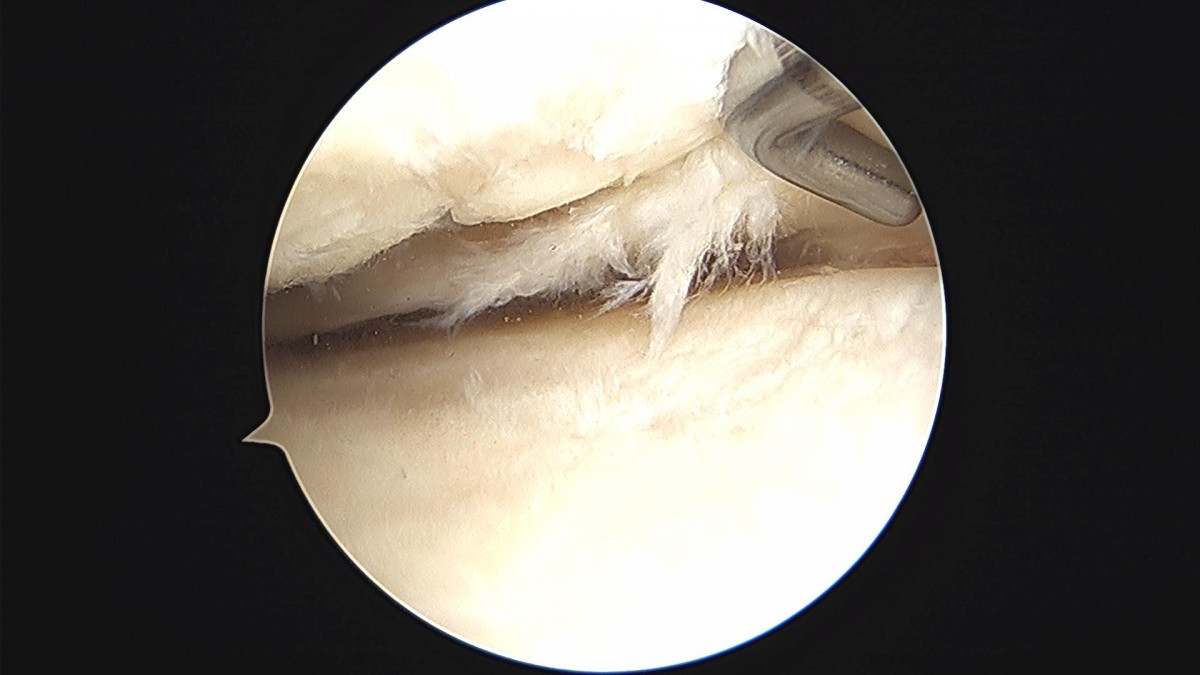

배우한원장님 무릎 내측 반월상 연골판 절제술 및 경골 교정술 장인O 환자

bccafb0c4c611c3a9fcb6ca752df8d40_1670487767_017.jpg

bccafb0c4c611c3a9fcb6ca752df8d40_1670487788_2302.jpg

bccafb0c4c611c3a9fcb6ca752df8d40_1670487801_2018.jpg

bccafb0c4c611c3a9fcb6ca752df8d40_1670487801_8893.jpg

bccafb0c4c611c3a9fcb6ca752df8d40_1670487802_5713.jpg

bccafb0c4c611c3a9fcb6ca752df8d40_1670487803_2439.jpg

bccafb0c4c611c3a9fcb6ca752df8d40_1670487803_9275.jpg

bccafb0c4c611c3a9fcb6ca752df8d40_1670487804_6306.jpg

bccafb0c4c611c3a9fcb6ca752df8d40_1670487805_3029.jpg

bccafb0c4c611c3a9fcb6ca752df8d40_1670487806_0258.jpg

bccafb0c4c611c3a9fcb6ca752df8d40_1670487806_7314.jpg

bccafb0c4c611c3a9fcb6ca752df8d40_1670487807_4518.jpg